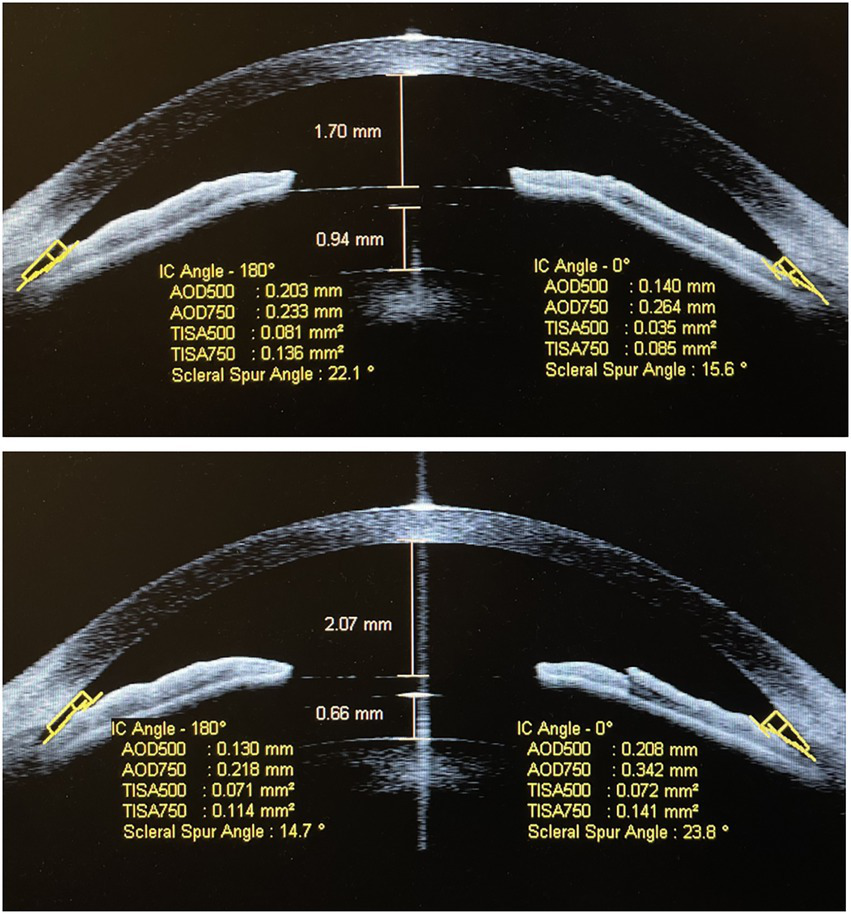

Figure 2

Anterior segment OCT image shows that the implantable collamer lens (ICL) vault was 940 μm and the anterior chamber depth was 1,700 μm before rotation (A) in patient A; 1 week after the rotation, the ICL vault was 660 μm and the anterior chamber depth was 2,070 μm (B).

Figure 3

Anterior segment OCT image shows that the ICL vault was 1,090 μm and the anterior chamber depth was 1,990 μm before rotation (A) in patient B; 1 week after the rotation, the ICL vault was 700 μm and the anterior chamber depth was 2,420 μm (B).

The mean vault value had declined significantly from 951.81 ± 154.26 μm pre-rotation to 772.27 ± 119.40 μm 1-week post-rotation (p < 0.001). The SSA, AOD500, AOD750, TISA500, and TISA750 at 180° and 0° pre-rotation and 1-week post-rotation were 30.40 ± 7.91° and 45.14 ± 6.75°, 32.37 ± 7.48° and 46.23 ± 6.39°, 303.27 ± 87.99 and 522.45 ± 122.16 μm, 323.81 ± 89.15 and 536.13 ± 121.66 μm, 387.95 ± 99.43 and 630.81 ± 133.59 μm, 435.68 ± 106.72 and 643.36 ± 132.82 μm, 0.109 ± 0.034 and 0.202 ± 0.053 mm2, 0.123 ± 0.034 and 0.212 ± 0.051 mm2, 0.194 ± 0.056 and 0.345 ± 0.083 mm2, and 0.216 ± 0.055 and 0.358 ± 0.079 mm2 (all p < 0.001; Supplementary Table 2; Figure 1). Anterior segment OCT image shows that the vault had declined significantly 1-week post-rotation, and the SSA, AOD500, AOD750, TISA500, and TISA750 at 180° and 0° had increased significantly accordingly (Figures 2, 3).